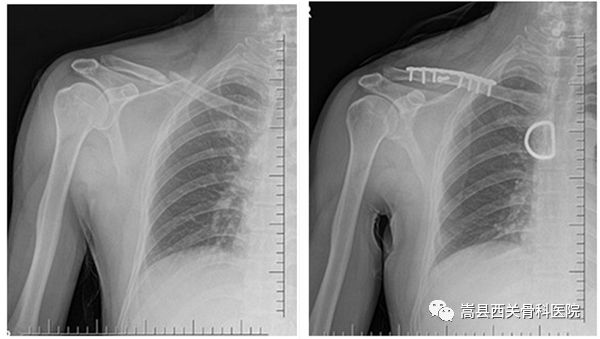

我院上肢创伤科部分患者术前术后对比图